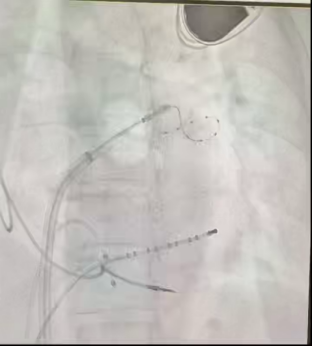

术前将DSA显示系统调整为180°镜像模式。术中,局部麻醉下建立股静脉通路,右侧置入2极和可调弯10极,左侧置入房间隔穿刺系统,通过造影剂确认房间隔穿刺成功,保留导丝置换冷冻球囊系统到左房,依次对左上、左下、右上、右下肺静脉进行冷冻消融,在冷冻至右上肺静脉过程中,转为窦性心律,四根肺静脉房颤相关电位脱落明确,起搏验证确定双侧肺静脉电位隔离,手术顺利完成。

四根肺静脉冷冻消融图